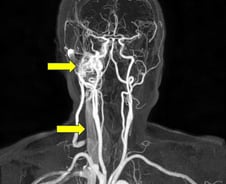

귀에서 심장 박동 소리처럼 반복적인 두근거림이 들린다면 이를 '박동성 이명'이라고 한다. 이 소리가 장기간 들린다면 단순한 이비인후과적 문제가 아니라 심각한 혈관성 질환이나 전신성 질환의 신호일 수 있다. 과연 박동성 이명은 어떤 병의 지표일 수 있을까? 서울특별시보라매병원 이비인후과 김영호 교수의 도움말로, 박동성 이명에 대해 알아본다. ━혈류 변화나 구조 이상으로 맥박성 소리 들려━박동성 이명은 귀에서 자기의 심장 박동과 같은 리듬의 소리가 반복적으로 들리는 상태다. "삐-", "윙-"등 일반적인 이명 소리와 달리 "두근두근", "둥둥둥" 같은 맥박성 소리가 특징적이다. 박동성 이명은 일반적인 이명과 달리 실제 혈류 변화나 신체 구조적 문제 같은 객관적 요인이 있을 가능성이 커, 정확한 진단과 원인 규명이 필수다. 박동성 이명은 일반적인 이명보다 발생 빈도는 낮지만, 전체 이명 환자 가운데 많으면 10%까지도 차지할 정도여서 무시할 수 없는 질환이다. 하지만 일반적인 이명과 달리